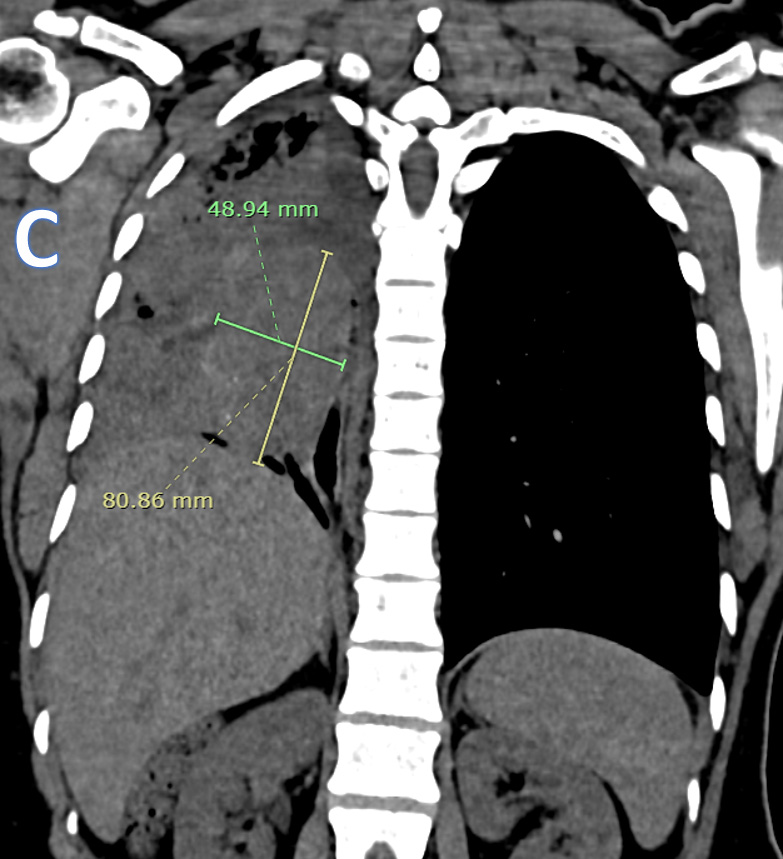

C – CORONAL CT THORAX

Ovoid heterogeneously isodense mass lesion with multiple tiny peripheral specks of calcifications in the right hemithorax with endobronchial extension.